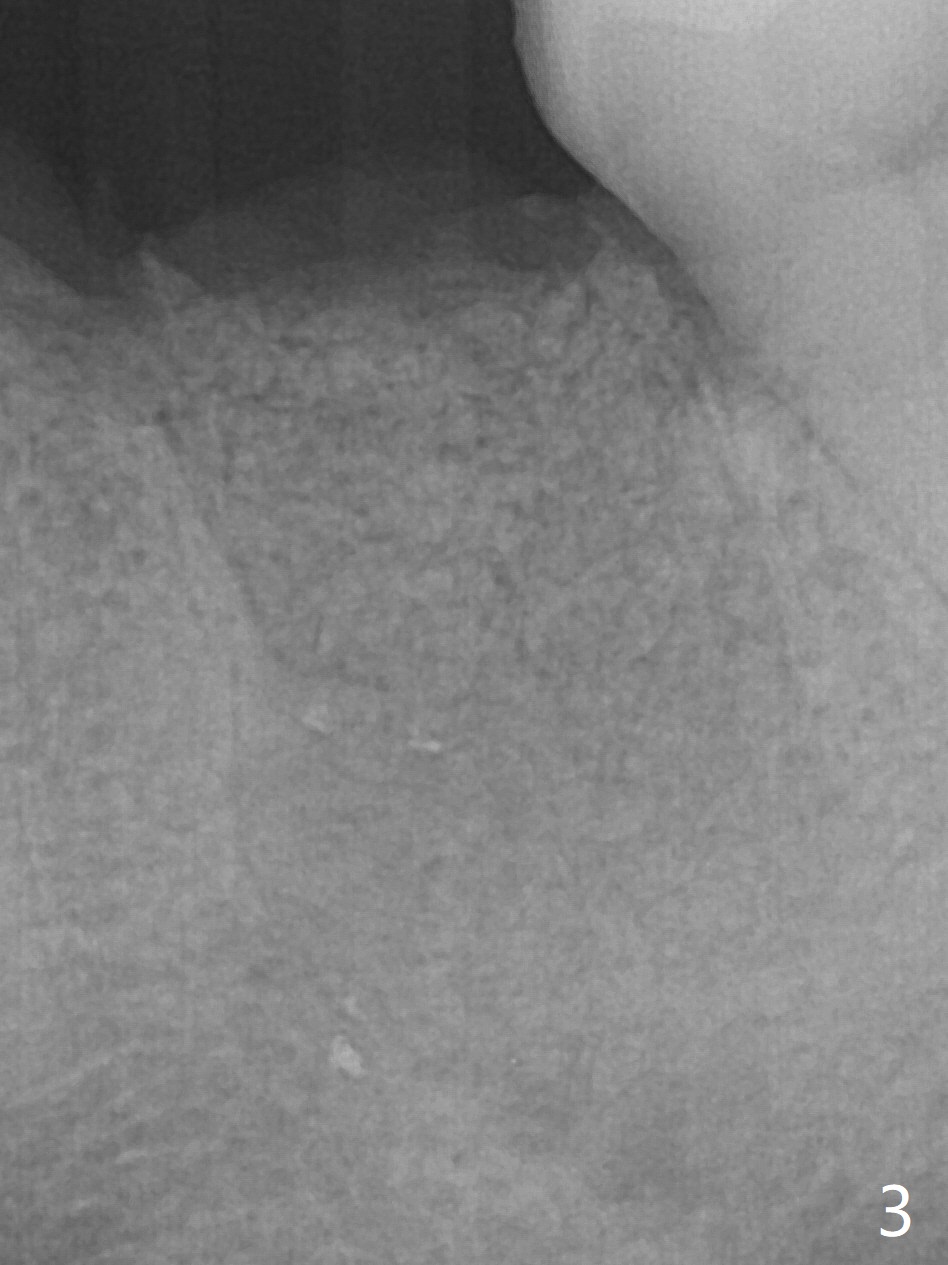

Extraction of the tooth #19 with large PARL (Fig.1,2) confirms the loss of buccal plate, but the crestal bone exists. After failure to place an implant in the middle socket with removal of the lingual septal bone, socket preservation is done with PRF and sticky bone (Fig.3). There is possibility to place a ~4 mm implant in the mesial socket (Fig.4). Or just drop a 5x11 mm Bicon Implant into the large socket, surrounded by sticky bone. When periodontal dressing is removed 18 days postop, the bone graft seems to remain to be "sticky" yellowish, while the granulation tissue has started to grow into the center of the socket from the previously buccal and lingual furcae (Fig.5 reddish). Granulation tissue seems to cover the bone graft (Fig.6), although there is smells when the periodontal dressing is removed. Bone height reduces nearly 3 months postop (Fig.7). The buccal plate collapses (Fig.8), but there seems no further bone loss 4 months postop (Fig.9). Because of buccal plate loss, an implant will be placed lingually with guide (Fig.10-12 green). Bone graft may be placed buccally after implant placement with probing.